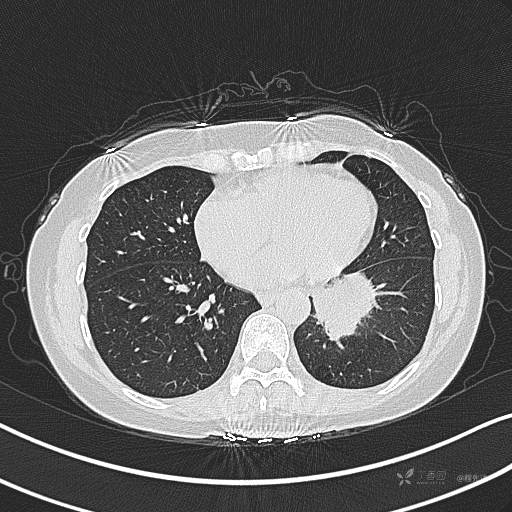

CT平扫

肺窗